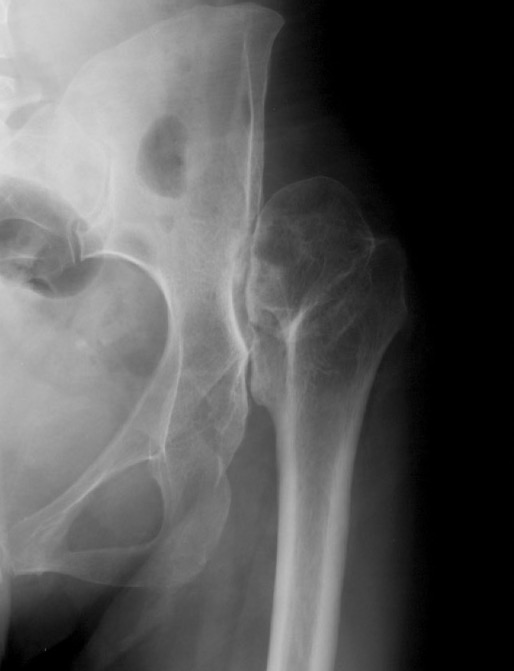

Crowe II / III: Medialize cup, superolateral femoral head augment, trochanteric slide

Acetabular component

Options

1. Restore normal hip center

- may need superolateral augmentation for stability wit Crowe II/III

2. High hip center

- allows coverage by native bone and decreases need for femoral shortening

- very small acetabular component with increased risk of loosening

Restore normal hip center

A. Recreate center of rotation

Place in true acetabulum

- transverse ligament is anatomical landmark

Medialise cup

B. Need for augmentation if > 30% uncoverage of acetabular component